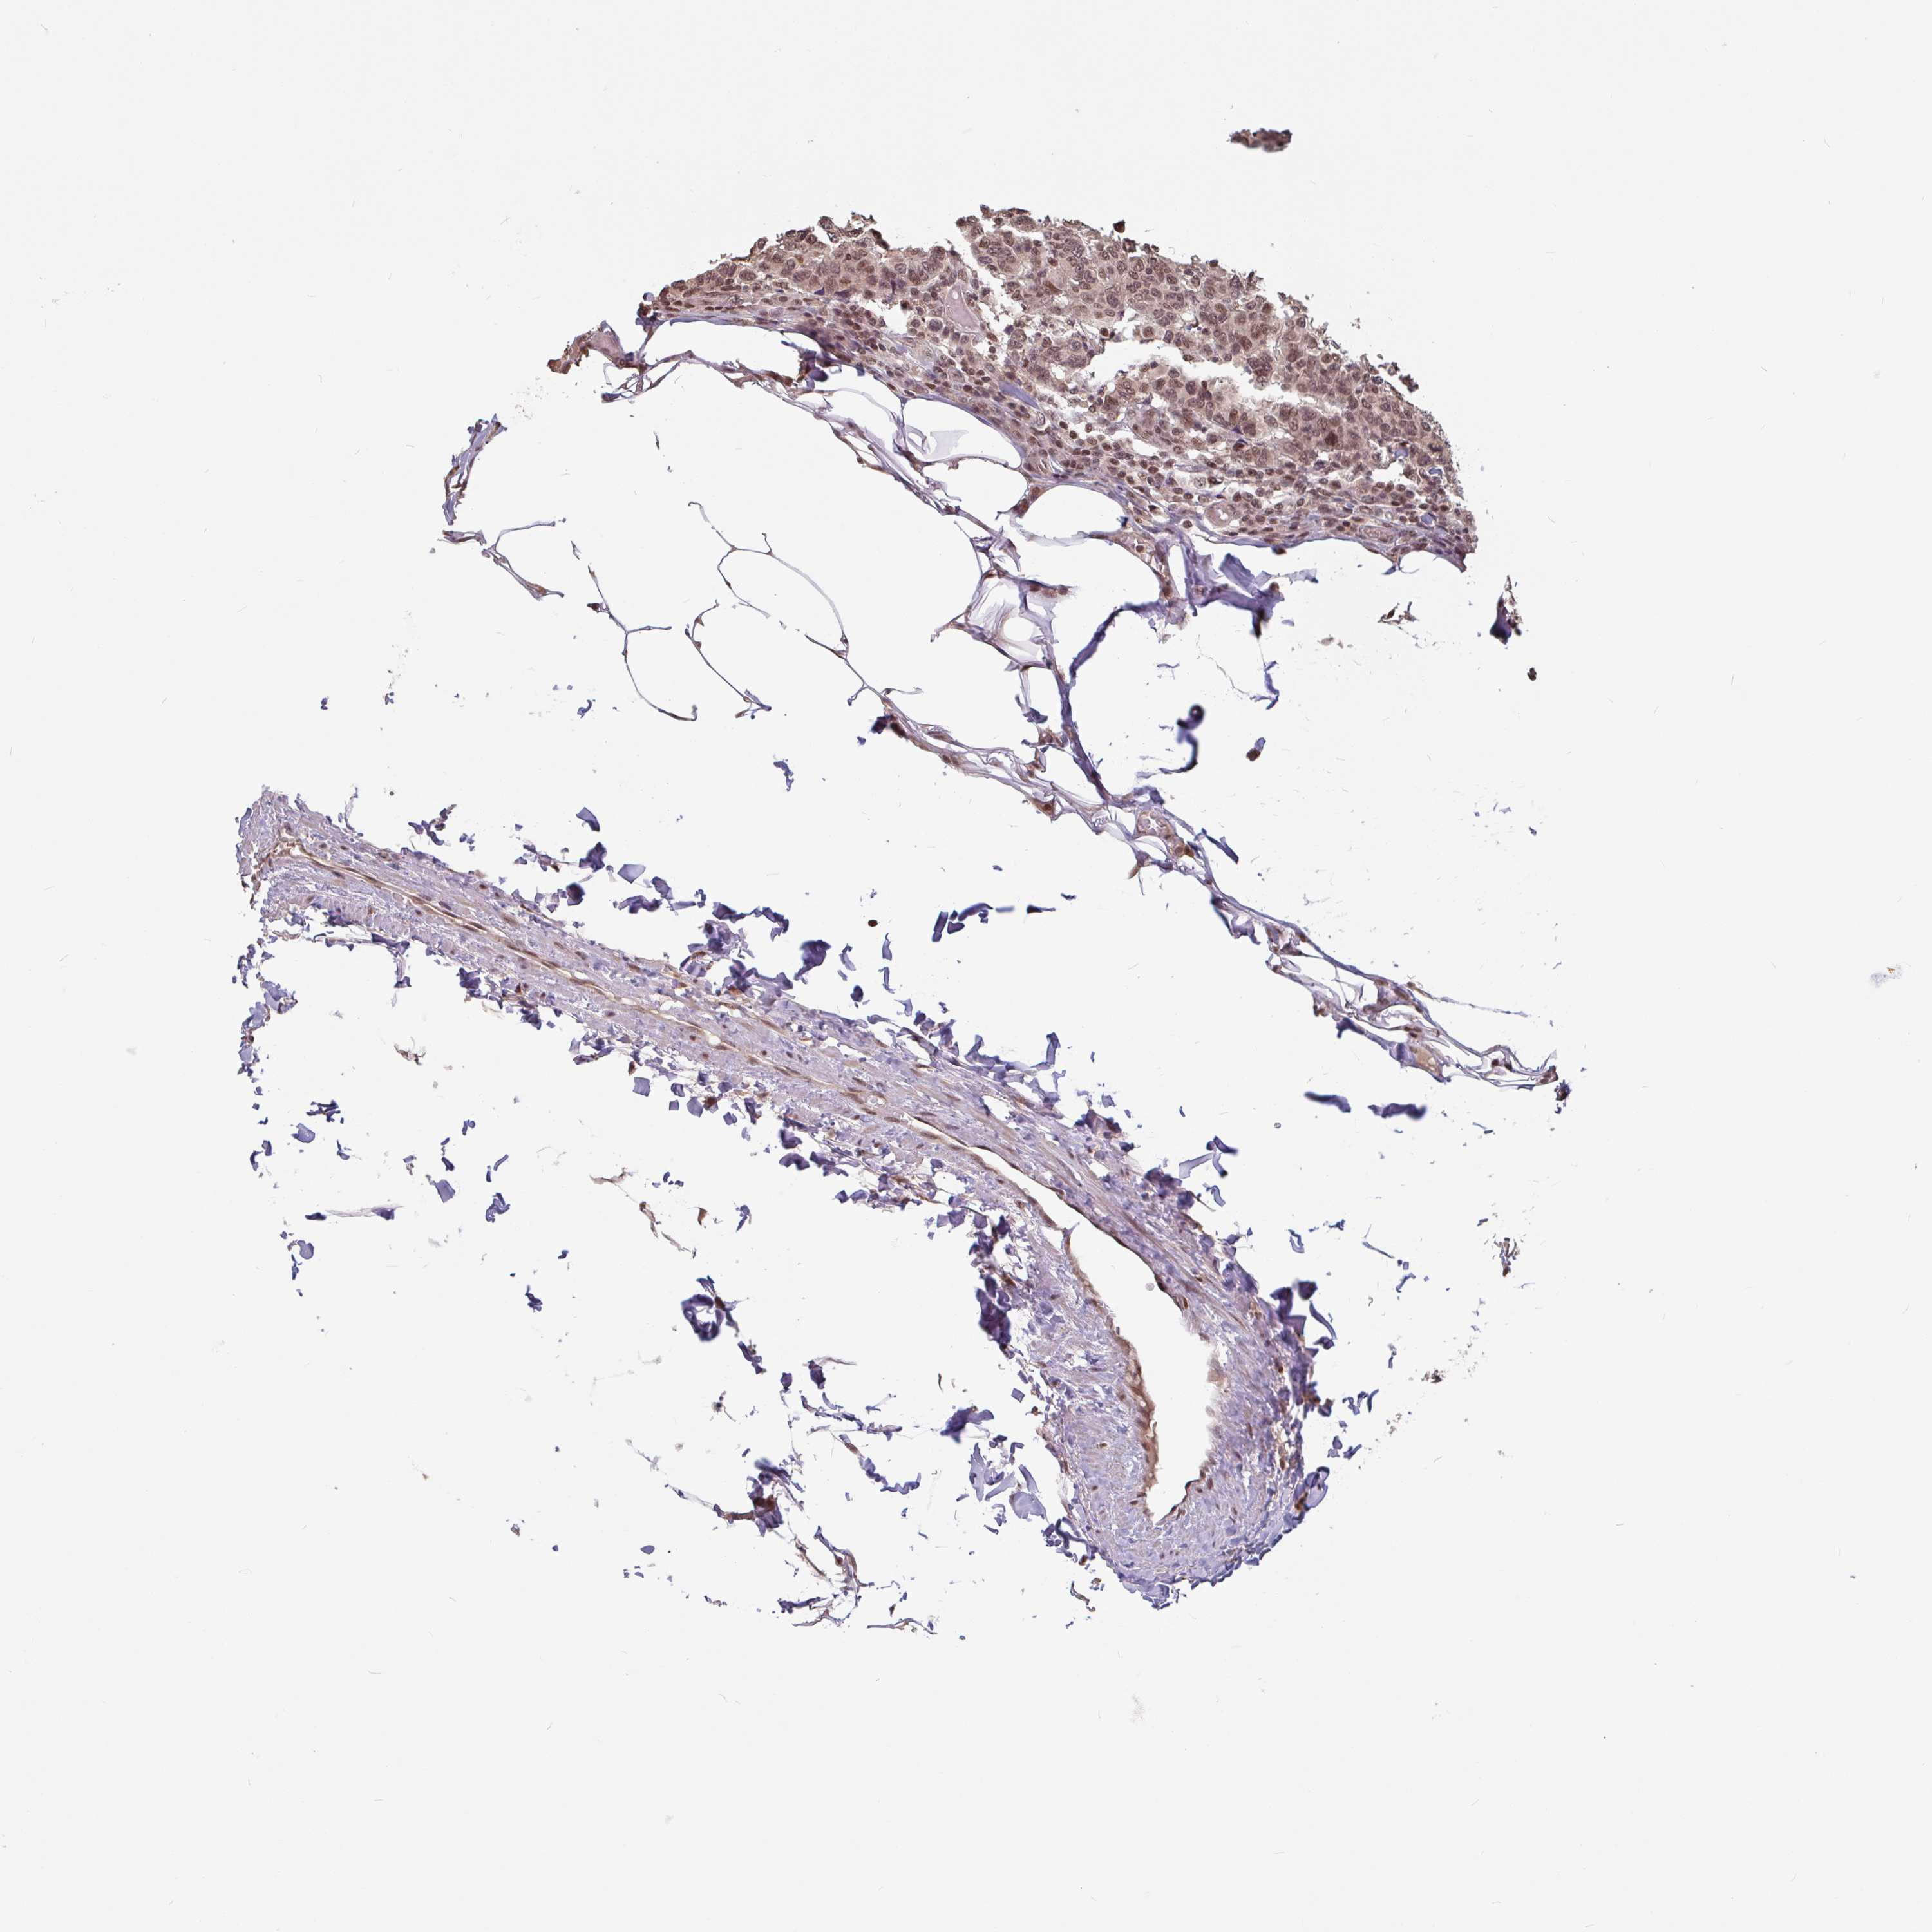

BRCA TCGA BRCA VALIDATION PROTEIN EXPRESSION

ANTIBODIES

AND

VALIDATION